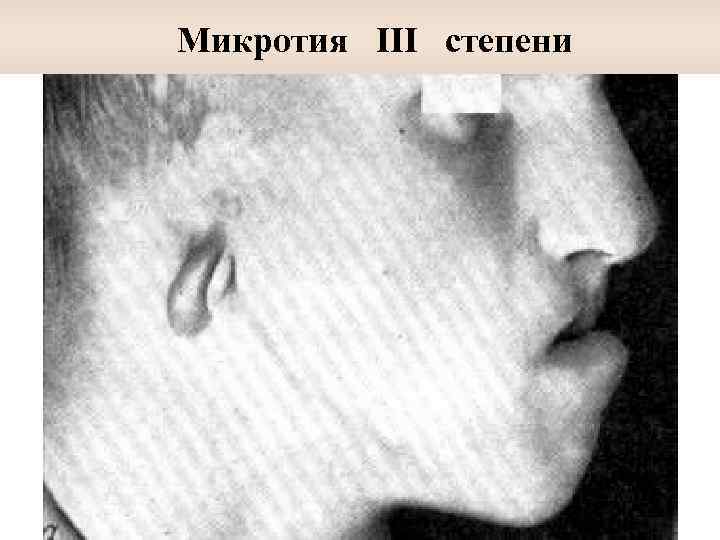

Микротия III степени